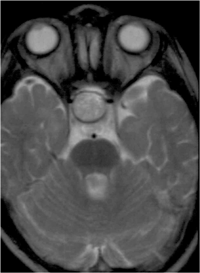

Glioma del nervio óptico

La edad de presentación típica es alrededor de los 9 años y afecta a ambos sexos por igual. El 75% de los gliomas del nervio óptico se presentan en la primera década de la vida y el 90% en las dos primeras. La prevalencia de neurofibromatosis tipo 1 (NF-1) en pacientes con glioma de la vía óptica varía según las series entre el 10 y el 70%. En la NF-1 el glioma del nervio óptico puede ser multifocal y en ocasiones involucra ambos nervios (Figura 3).

Figura 3. Glioma nervio óptico que invade quiasma RMN T1.